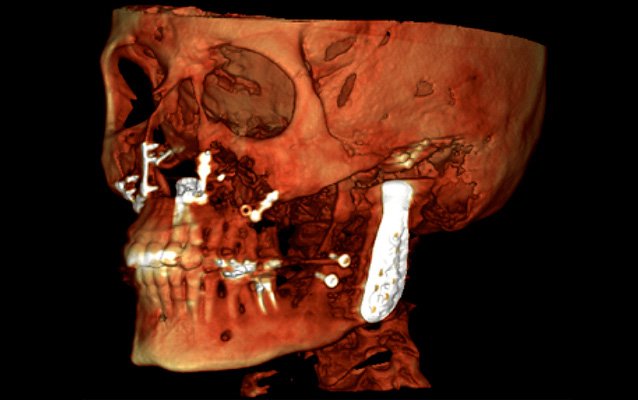

Protokół Planmeca Ultra Low Dose okazał się idealny do szerokiego zakresu zastosowań klinicznych, od ortodoncji do planowania implantów, chirurgii szczękowej oraz badań dróg oddechowych i zatok.

Planmeca Ultra Low Dose może być stosowany ze wszystkimi rozmiarami wokseli i wszystkimi trybami obrazowania, od najmniejszego rozmiaru woksela do największego pola widzenia (FOV). Ten protokół obrazowania jest idealny, gdy wymagane są szczegółowe informacje anatomiczne przy bardzo niskich dawkach promieniowania.

W pełni innowacyjny i naukowo zatwierdzony protokół obrazowania oparty na inteligentnych algorytmach 3D znacznie zmniejsza dawkę dla pacjenta bez pogorszenia jakości obrazu, zapewniając klinicystom na całym świecie możliwość skutecznego stosowania ALADY (minimalnej akceptowalnej diagnozy). Dążymy do tego, aby mieli taką możliwość. Stosowanie i skuteczność Donk Eye zostało naukowo zbadane i udowodnione w różnych badaniach.

Wysoka rozdzielczość i duża dawka nie zawsze są niezbędnymi standardami i często mniej znaczy więcej. Na przykład obrazowanie ultraniskodawkowe Planmeca jest niezbędne do uwidocznienia kanału nerwu żuchwowego przy planowaniu implantów i ekstrakcji zębów mądrości. Wszystko to można osiągnąć przy wyjątkowo niskich dawkach.